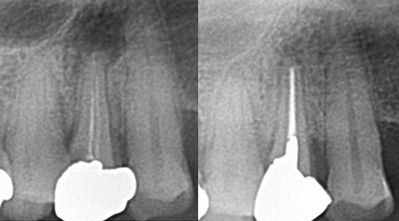

根管治療

根管治療は歯の土台の治療です。

当医院では時間をかけ丁寧に治療します。

ステンレス、ニッケルチタン等のファイルを使用し、再治療を極力減らすよう努めています。

また次亜塩素酸及びEDTAを用いた洗浄

水酸化カルシウムを用いた根管消毒

微少漏洩(細菌の進入)の無い緊密な仮封

を行っています。